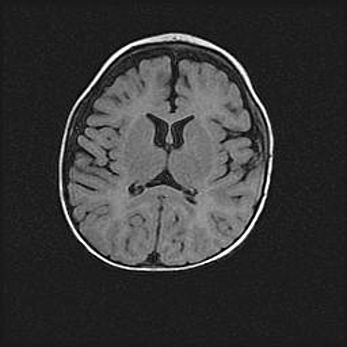

Открытая гидроцефалия.

Возраст: 9 месяцев 12 дней

Вес: 6800 г

Пол: мужской

Окружность головы: 41,5 см

Срок гестации: 28 недель

Гидроцефалия головного мозга у новорожденных имеет характерный признак: опережающий рост окружности головы приводит к визуально хорошо определяемой гидроцефальной форме сильно увеличенного в объёме черепа. Детские неврологи определяют следующие симптомы гидроцефалии у грудничков: выбухающий напряжённый родничок, частое запрокидывание головы, смещение глазных яблок к низу.